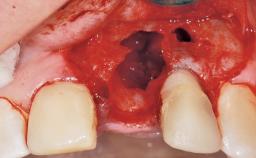

Late Placement of an Implant in a Maxillary Left Central Incisor Site

A 30-year-old female patient had lost tooth 21 and was referred to our clinic for consultation and treatment. Due to advanced apical infection, tooth 21 had been extracted two months earlier at another clinic and an acrylic-resin tooth had been bonded to the adjacent teeth. The patient desired implant treatment to avoid any damage to the adjacent natural teeth. While the patient had no history of any systemic disorder, she was a heavy smoker and exhibited medium to advanced periodontitis in the entire jaw. After the initial treatment to achieve a pocket probing depth of less than 4 mm and no bleeding on probing, a decrease in the height of the papillae mesial and distal to the extraction site and overall gingival recession were observed.

Bone Augmentation Horizontal|Staged

Augmentation Materials Autogenous chips|Membrane

Soft Tissue Grafting Simultaneous

Soft Tissue Anatomy Intact Defective

Bone Volume Horizontally and vertically sufficient Horizontally deficient Deficient vertically or deficient vertically AND horizontally